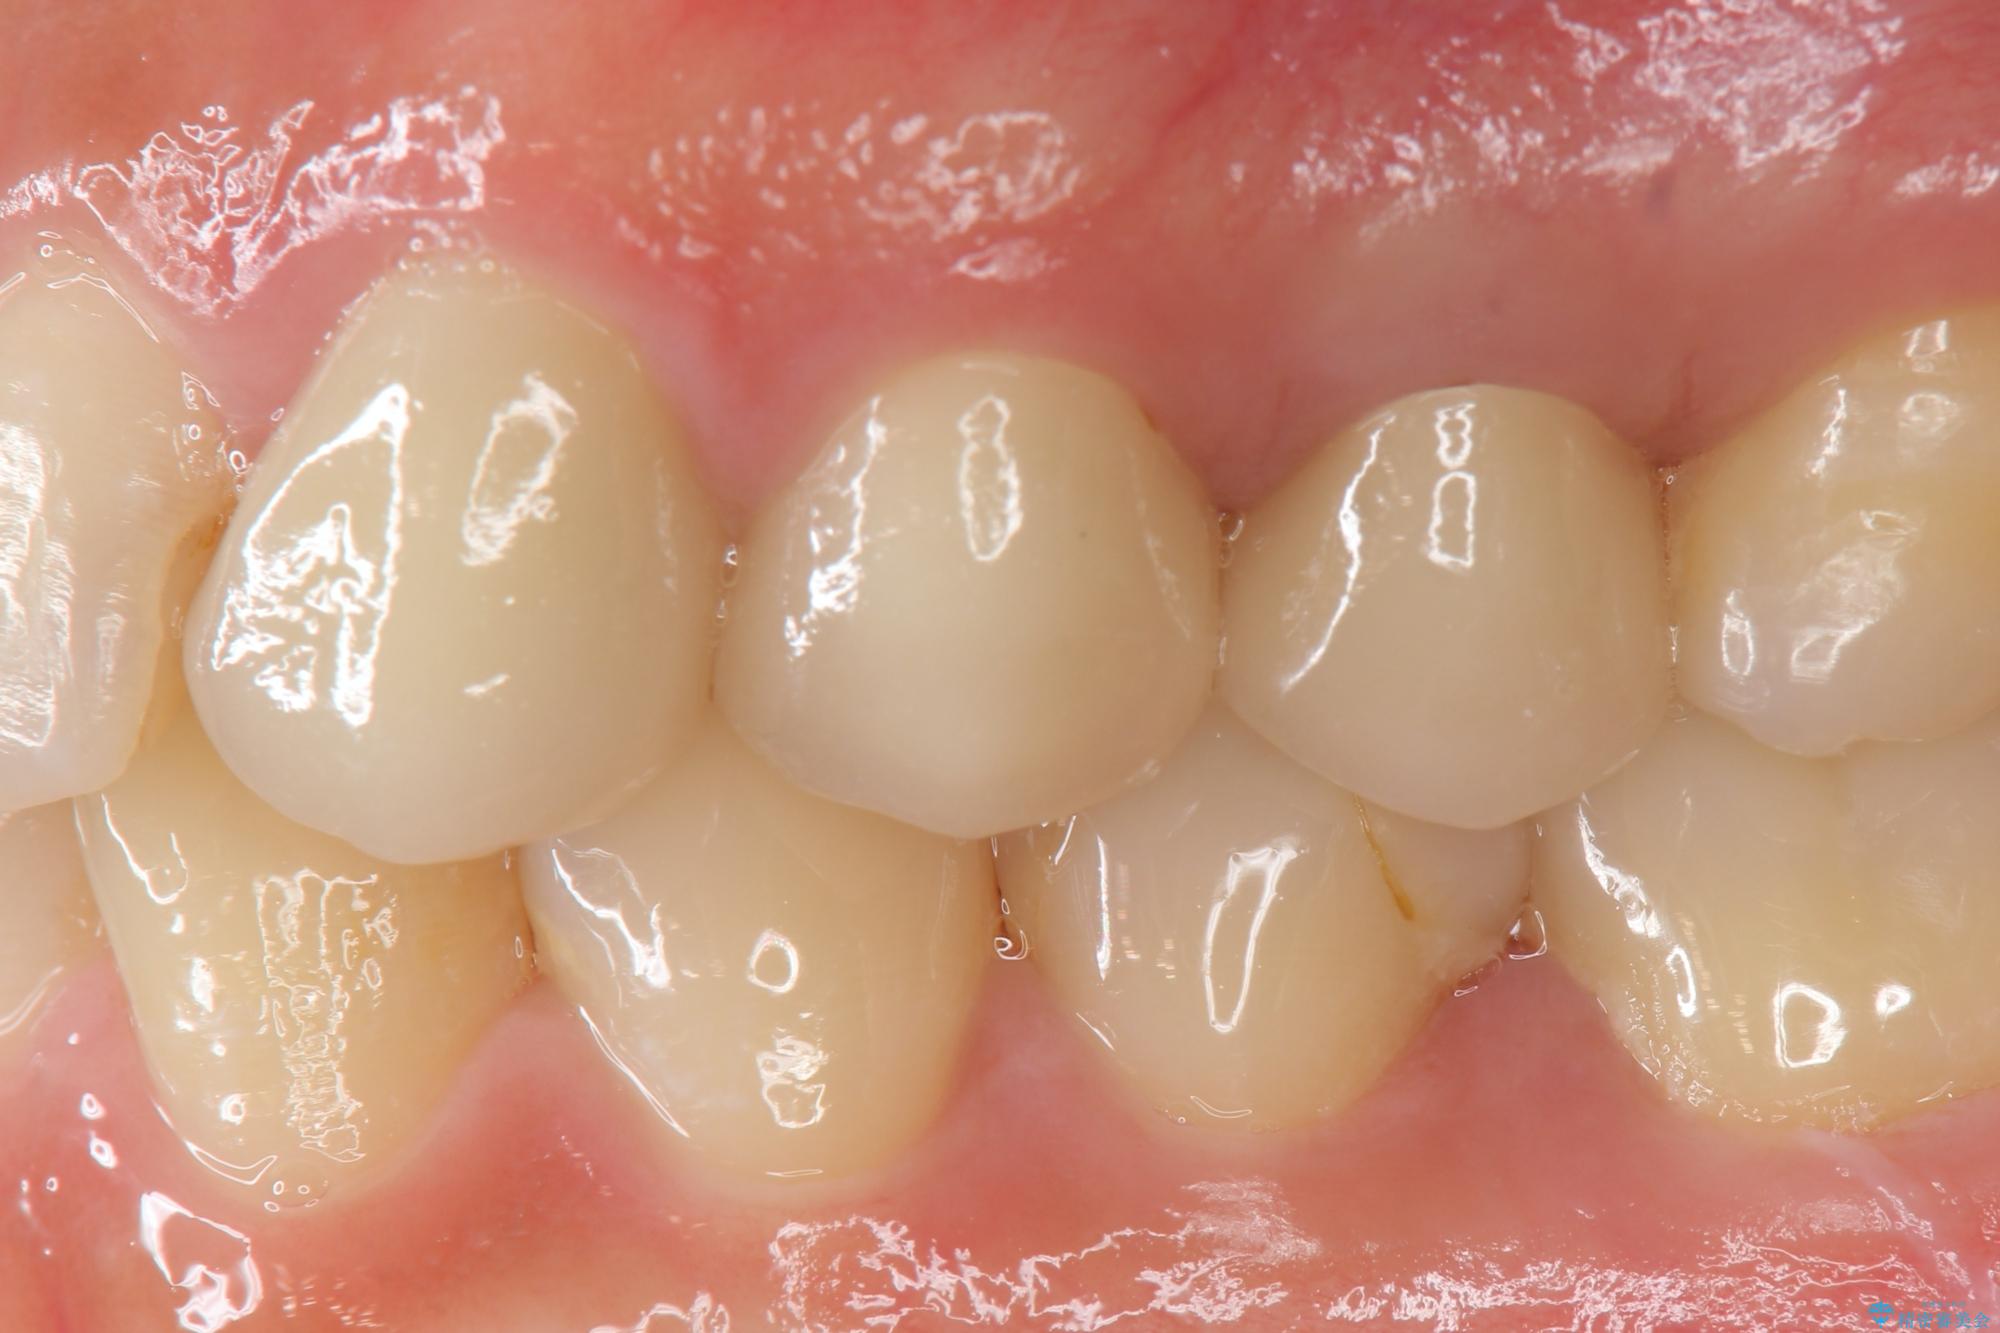

歯の水平・垂直的位置を整備したセラミッククラウン治療

当初、歯ぐきよりも深い虫歯のぞんざいや、歯のポジションに問題がありましたがマルチブラケットを用いた部分矯正を行うことで適切な位置へと歯を移動させ、歯周環境を整えたセラミック治療を行うことができました。